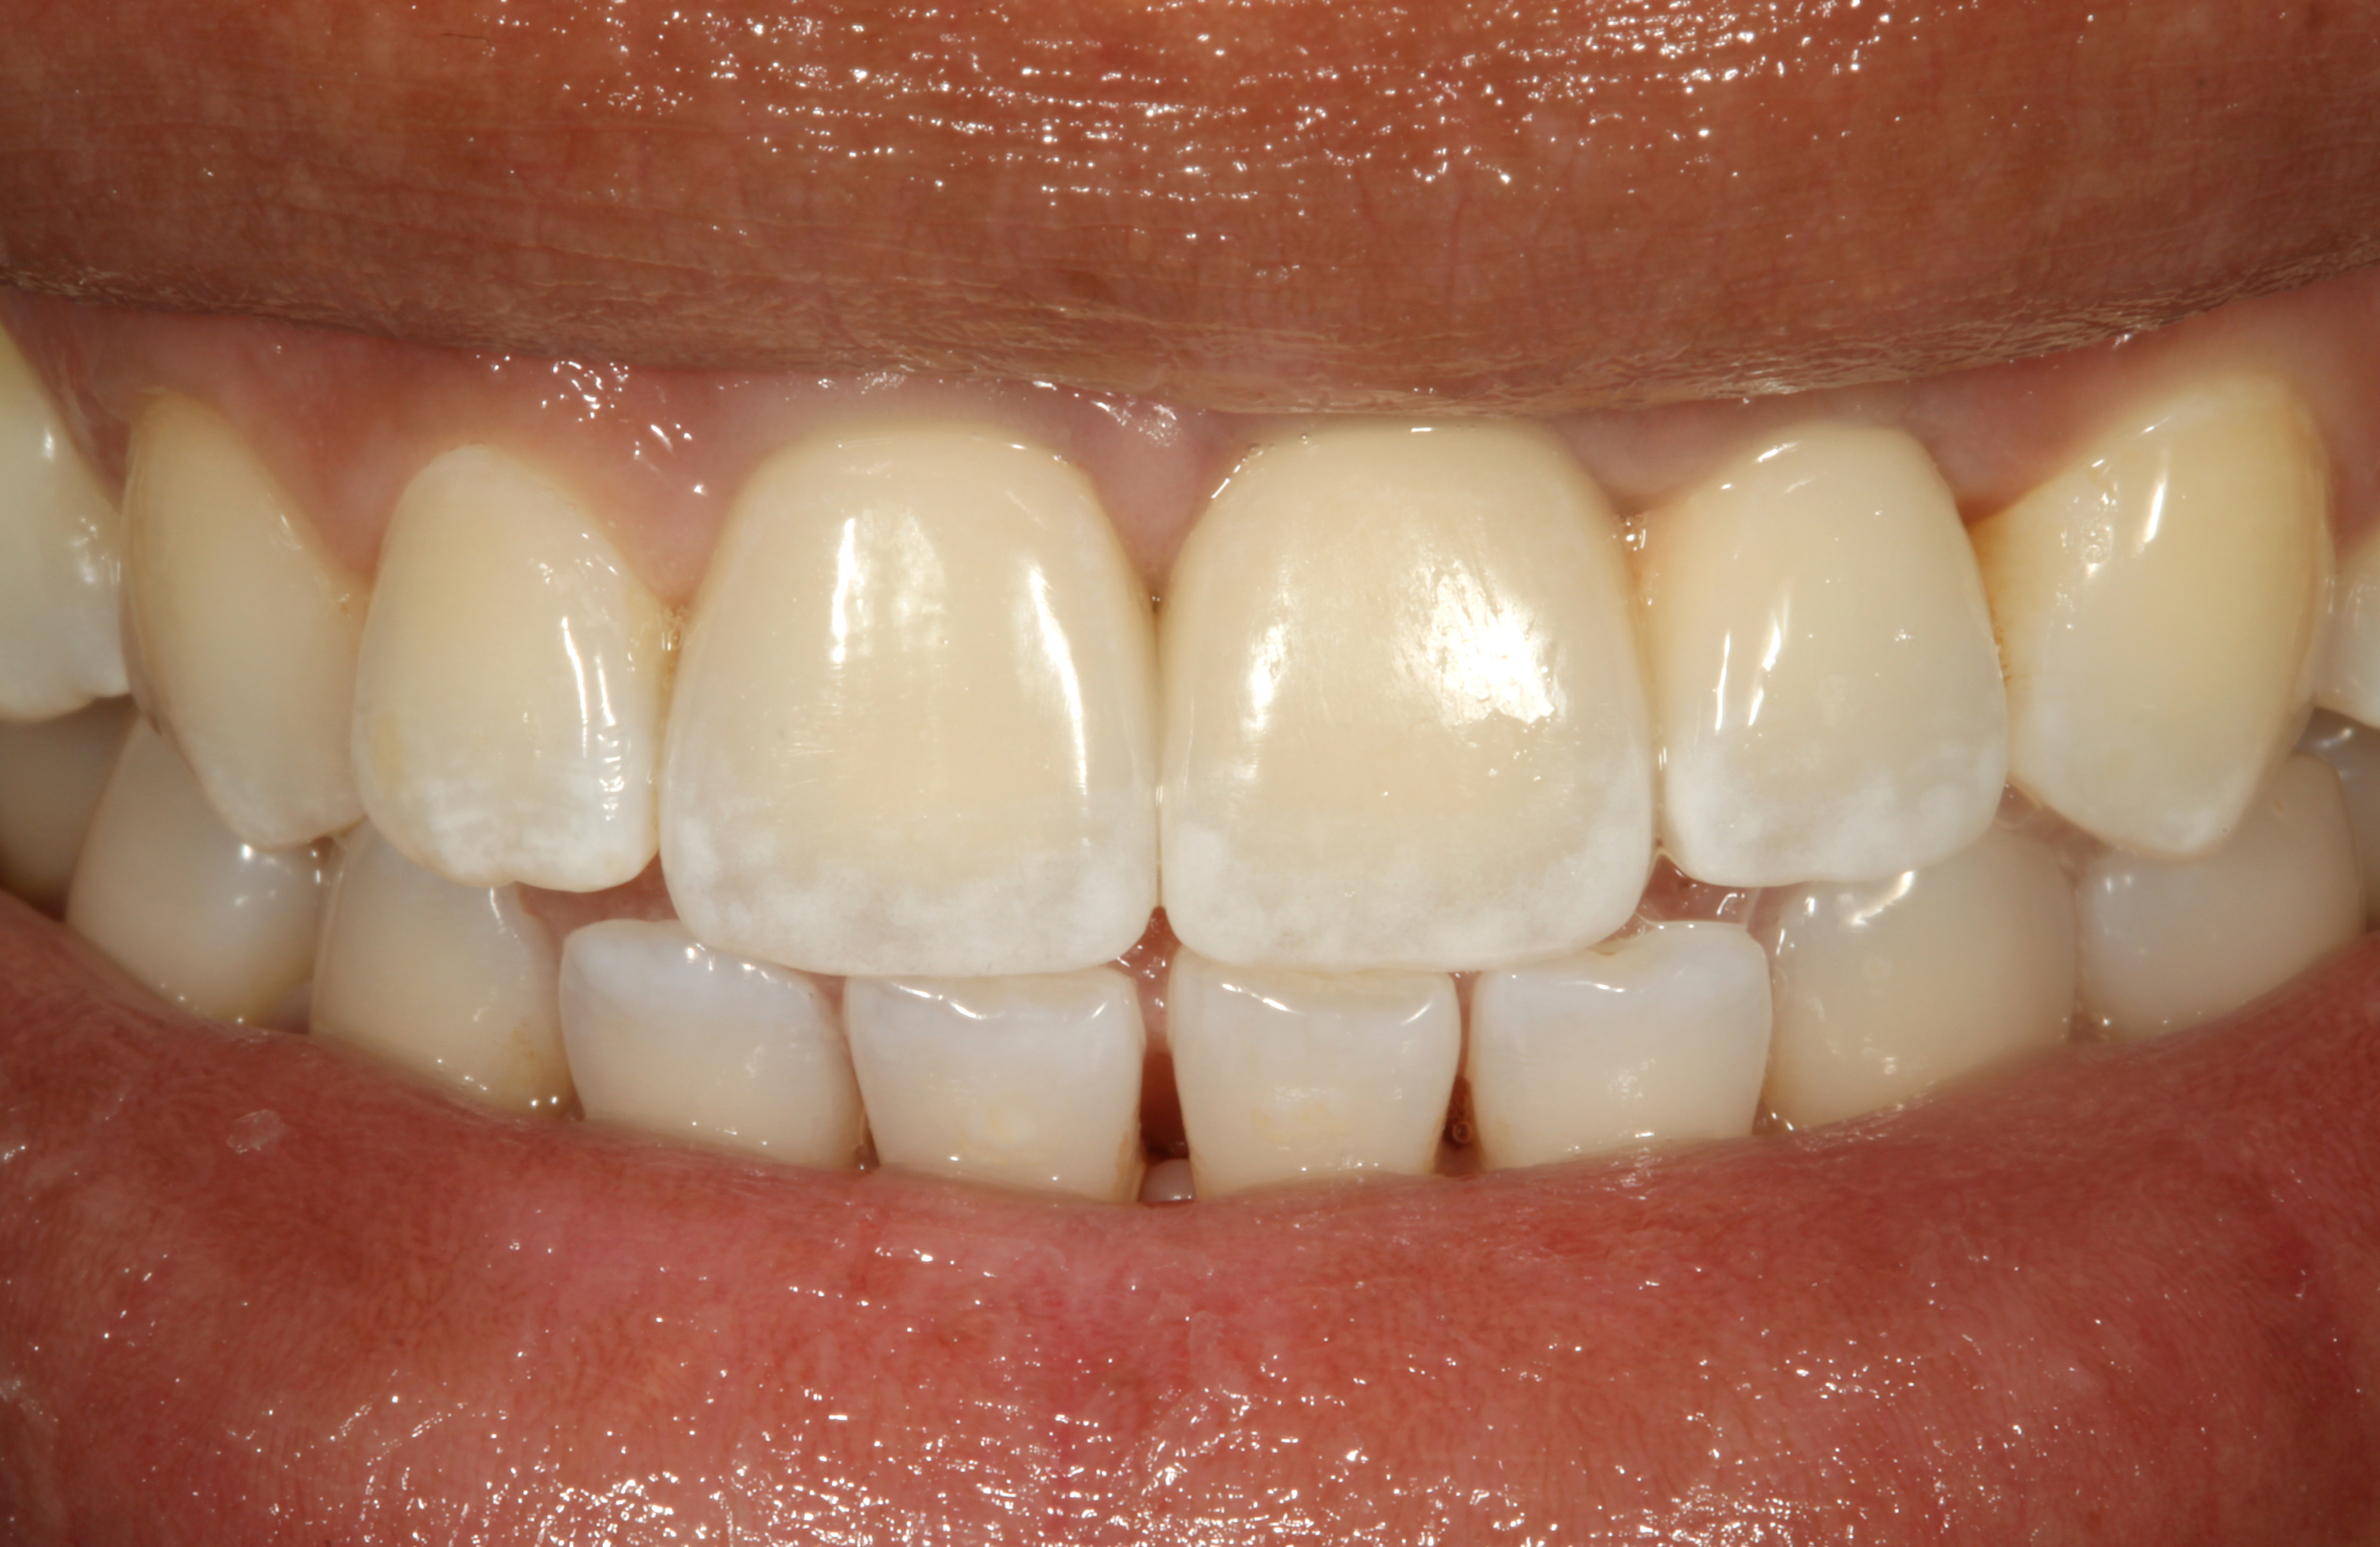

The resolution of the inflammatory aspect of the peri-implantitis lesion (Figure 26) was evidenced by 3-mm pocketing and an absence of bleeding upon probing. A 17-month follow-up (Figure 27) demonstrated resolution of the mucogingival problem, as evidenced by a deepened buccal vestibule, a zone of keratinized gingiva, and correction of the recession. A 17-month post-treatment radiograph (Figure 28) showed bone fill with elimination of the infrabony component of the lesion. Even with the close bone-to-implant approximation evident, a claim of osseous regeneration cannot be validated without histologic verification.

Fig 26. Nine-month follow-up showing a 3-mm probing depth and an absence of bleeding on the buccal of treated implant No. 19.

Figure 26

Fig 27. Seventeen-month follow-up showing keratinized gingiva at the free gingival margin, resolution of the recession defect and deepening of the vestibule.

Figure 27